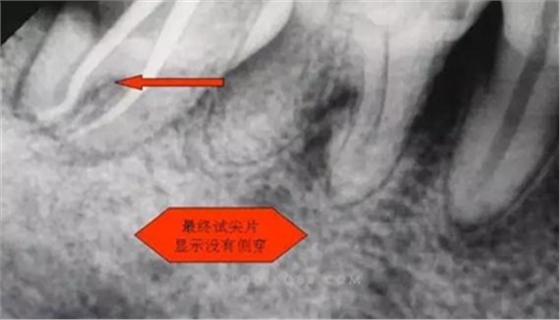

圖三

剛開始懷疑有增生的牙體組織,其實就是髓石。

1.拍片基本可以確定遠中頰側(cè)根管是一個融合根管,也就是常見的C型根管,粗大的根管口是扁形,根管同樣呈扇貝型,根尖孔粗大。而且在根管中上段較粗大,插針拍片后遠中顯示根管有側(cè)穿的可能,但是通過內(nèi)窺鏡顯示是沒有任何側(cè)穿點,也沒有滲血和患者有疼痛現(xiàn)象。這個病例告訴我們,有時候做根管治療,為了把根管做通和預備到位,必要的牙體組織去除是可以的,后期可以用冠修復來彌補,如果不去除,本病例的根管治療,根充時可能會面臨充填不嚴密,從而導致根管治療的失敗,這是不可取的。

6.本病例,由于連接近遠中2個根管的融合區(qū)頰舌徑過于狹窄,在x線片上顯示不清,而唯一能表現(xiàn)的是近遠中分離的2個獨立的根管,將K銼放置到頰側(cè)根管內(nèi),有時在x線片上表現(xiàn)出根分叉處可能穿孔,這也是C型根管在x線上的重要特征。